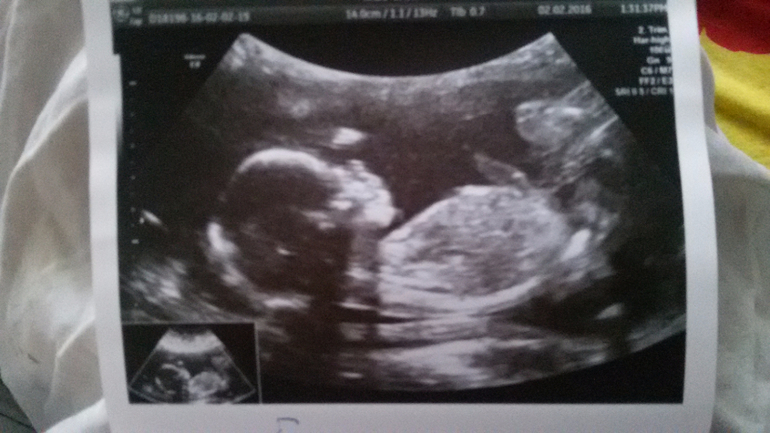

вот такими я их видела посл раз в 20 недель...